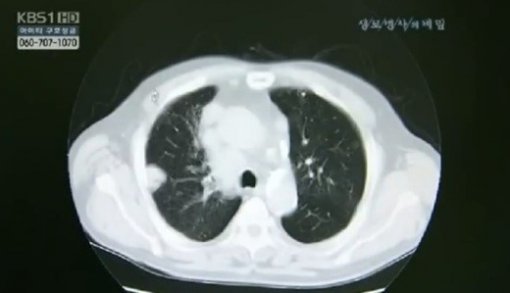

한국인 폐암 유형 1위 ‘선암’을 재발시키는 유전자가 발견돼 학계의 관심이 지대하다.

서울아산병원 암병원 폐암센터 장세진, 김형렬 교수팀은 지난 13일 한양대의대, 서울대 자연과학대 연구팀과 공동으로 폐절제술을 받은 폐선암 환자 247명을 대상으로 유전체를 분석했다.

실험 결과에 따르면 RB 유전자의 돌연변이가 한국인 폐암 유형 1위로 수술 후 조기 폐암의 재발에 영향을 미치는 것으로 확인됐다.

연구결과 RB 유전자에 돌연변이를 가진 환자가 폐암의 재발없이 지낼 확률은 20%로, RB 유전자에 변이가 없는 환자의 60%보다 훨씬 낮은 수치를 기록했다.

폐암은 국내 사망률 1위의 암으로 최근에는 폐의 선(腺)세포에 생기는 ‘선암’ 발병률이 국내 폐암 환자 중 40%를 차지했다.

조기 폐선암의 경우 1기라 할지라도 10~20%는 수술 후 재발하기 때문.

지금까지 폐선암 재발을 예측할 수 있는 특정 바이오마커는 규명되지 않았다. 이번 한국인 폐암 유형 1위 돌연변이 유전자의 발견으로 폐선암 재발 예측과 표적 약물치료 등 폐선암의 맞춤형 치료에 한발 더 다가설 수 있을 것으로 예상된다.